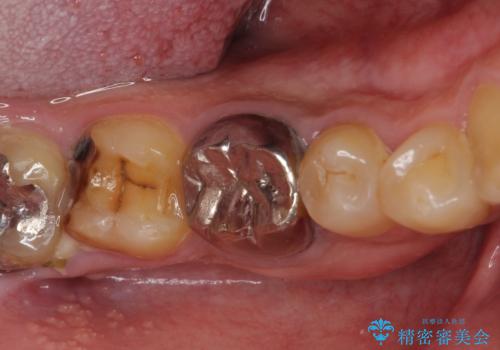

- 親知らずを抜くことが怖く、先送りにした結果親知らずの前の歯に大きな虫歯ができてしまったとのことで来院された患者様です。

親知らずは速やかに抜歯し、手前の歯とその前の歯に歯槽骨にまで及んだ虫歯が認められたため、歯槽骨を削るなどの歯周外科処置を行うこととしました。